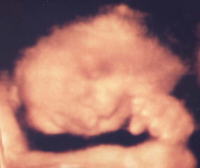

毎回の妊婦健診の際に、おなかの中の赤ちゃんの映像を3D超音波撮影にて専門の技師が撮影致します。(料金は無料)

小さな命の成長をしっかりと見守り続けてください。

< 3D超音波画像例 >